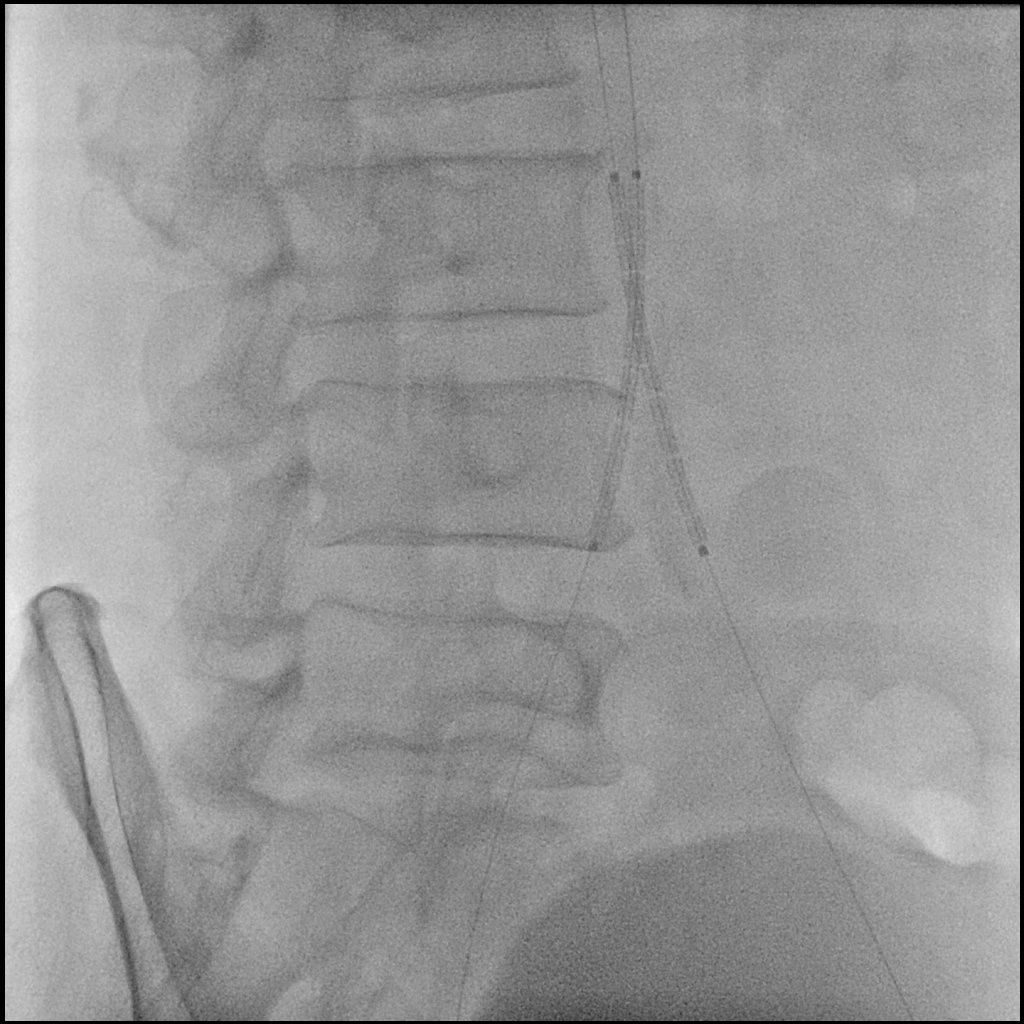

A 6F Mach1 MP guiding catheter waspositioned via aterial access. Wiring was performed sequentially with Gladius0.014¡È and Halberd 0.014¡È under NaviCross 0.018¡È catheter support, then switched to an Astato XS 40 for bettercontrol. Using a CSI microcatheter, the 0.018¡È system was exchanged for a 0.014¡È wire to performIVUS. IVUS initially could not advance but succeeded after predilatation withan Ultraverse 2.0 balloon. IVUS revealed that the lesion was locatedclose to the inferior mesenteric artery and provided accurate vessel sizing forappropriate stent selection. The system was then switched back to the 0.018¡È platform forintervention. Balloon dilatations were performed using Ultraverse 5.0 ¡¿ 80 mmfor the right and 7.0 ¡¿ 40 mm for the left common iliac artery, followed bysimultaneous kissing balloon inflation. Further expansion was achieved with Armada8.0 ¡¿ 80 mm balloons. Two VBX 8.0 ¡¿ 59 mm heparin-bonded stent grafts weredeployed in the right and left common iliac arteries. A subintimal flap belowthe right CIA stent edge required an additional VBX 8.0 ¡¿ 39 mm stent.Post-dilatation was performed with a Finestream S Plus 8.0 ¡¿ 40 mm andUltraverse 7.0 ¡¿ 80 mm balloon using the final kissing technique. Final angiography demonstrated well-expandedstents and excellent bilateral flow without residual stenosis or dissection.Both femoral access sites were closed with ProGlide devices, and the leftradial sheath was removed with manual compression.